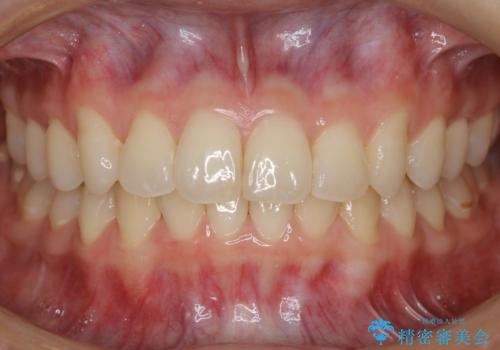

【非抜歯】結婚式に向けて矯正で素敵な笑顔を!

- 笑った時の歯の見え方を治したいとのことで矯正相談にいらっしゃいました。

一見そこまで大きなガタつきはないようにも見えますが、前歯の角度の不揃いや噛み合わせのズレなどから見え方に影響が出てしまっていました。

抜歯は全く必要のないレベルのガタつきだったため、マイクロインプラントを用いて歯全体を後方に移動させていくことできれいな歯並びを獲得することができました。

マウスピースとマイクロインプラントを組み合わせることで、抜歯をしなくても歯並びを治すためのスペースを作ることができます。奥歯から順に移動させていくので前歯に変化が出るまでには時間がかかりますが、どの分健康な歯を抜歯することなく理想的な歯並びを手に入れることができます。